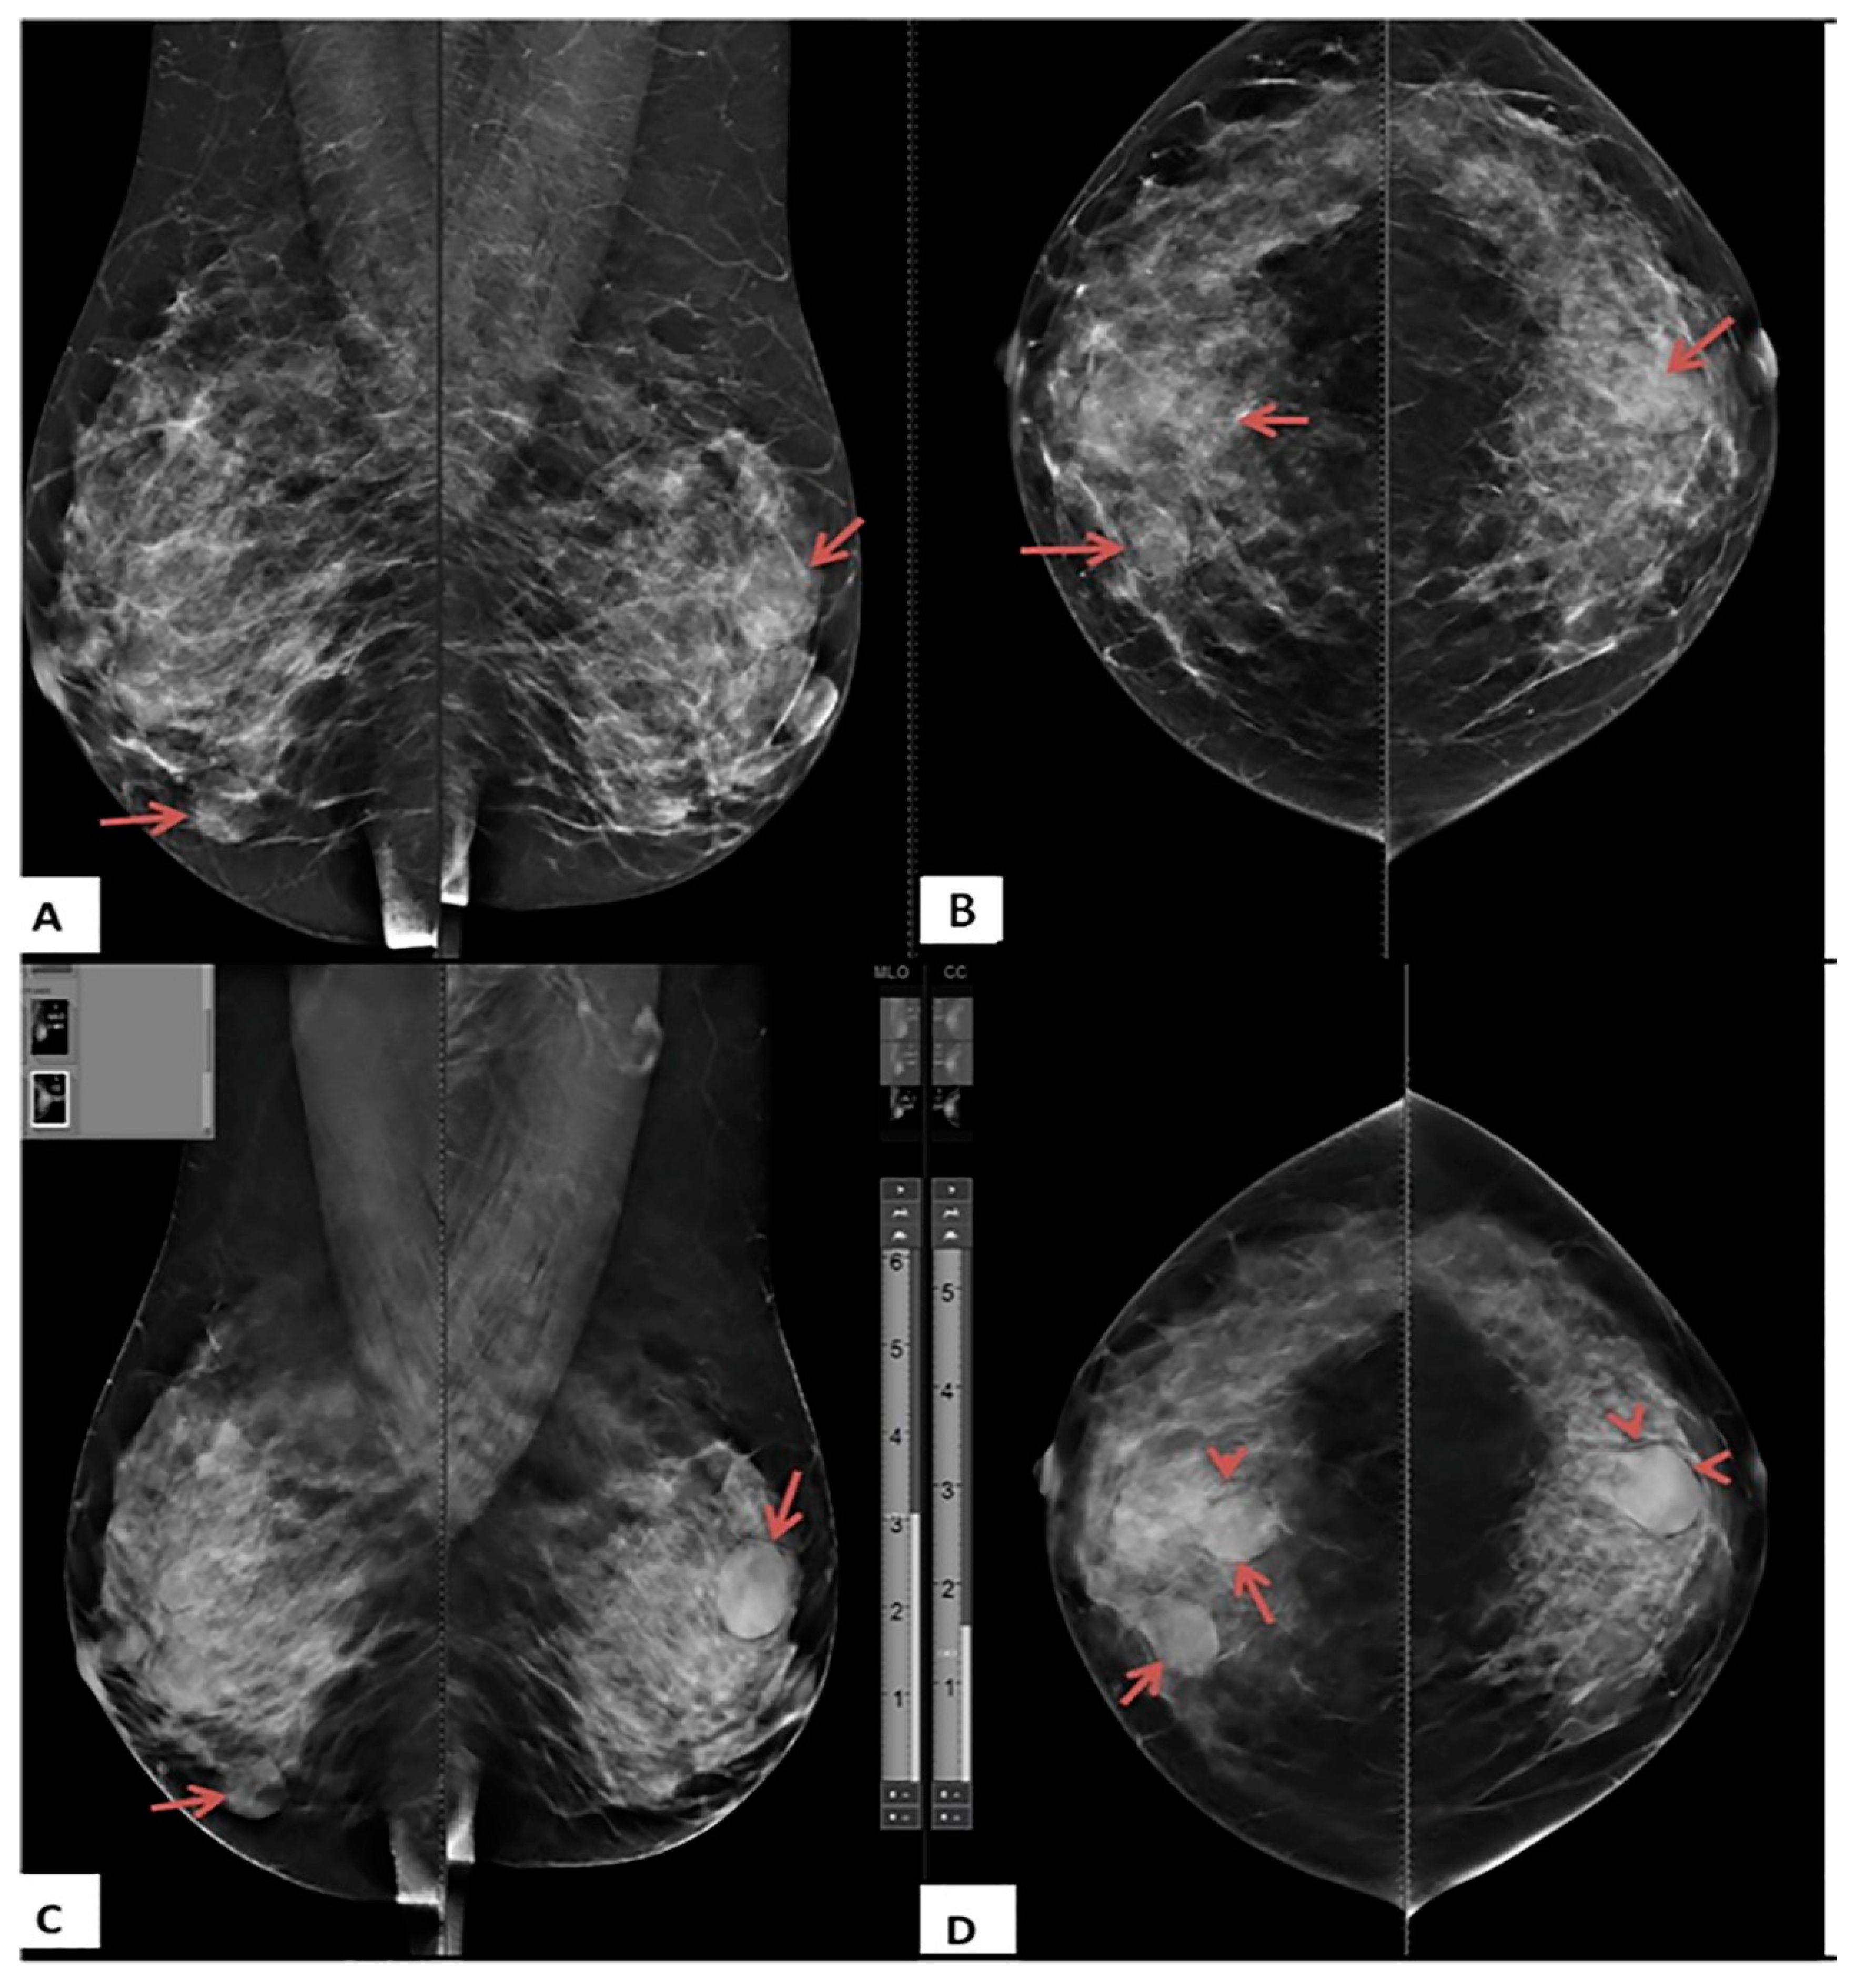

Figure 5. A 61-year-old female presented with right breast pain (A) Craniocaudal and (B) Mediolateral oblique DM images for both breasts show bilateral fatty breasts (ACR A). The upper inner quadrant of the right breast shows a small, oval, and ill-defined mass lesion (arrows). No microcalcifications (C) Craniocaudal and (D) Mediolateral oblique DBT images of the right breast show speculated margins of the right breast lesion (arrows). The lesion was classified as BI-RADS 3 based on DM and BI-RADS 4b based on DBT. Histopathological examination revealed invasive ductal carcinoma.